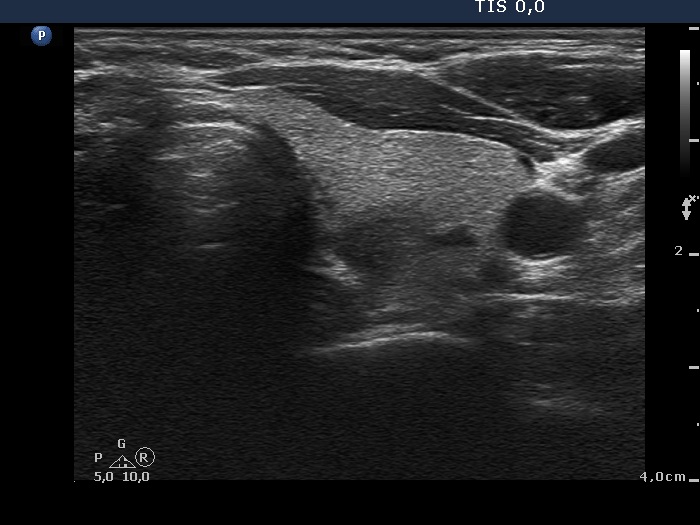

Follow-up 2 months after the first visit (3rd row of images):

Ultrasonography: The right lobe decreased in size as did the extent of hypoechogenic areas in this lobe. The left lobe remained unchanged.

Follow-up 6 months after the first visit (3rd row of images):

Ultrasonography: The pattern of the entire thyroid became almost completely normal. Only small hypoechoic areas were observed.